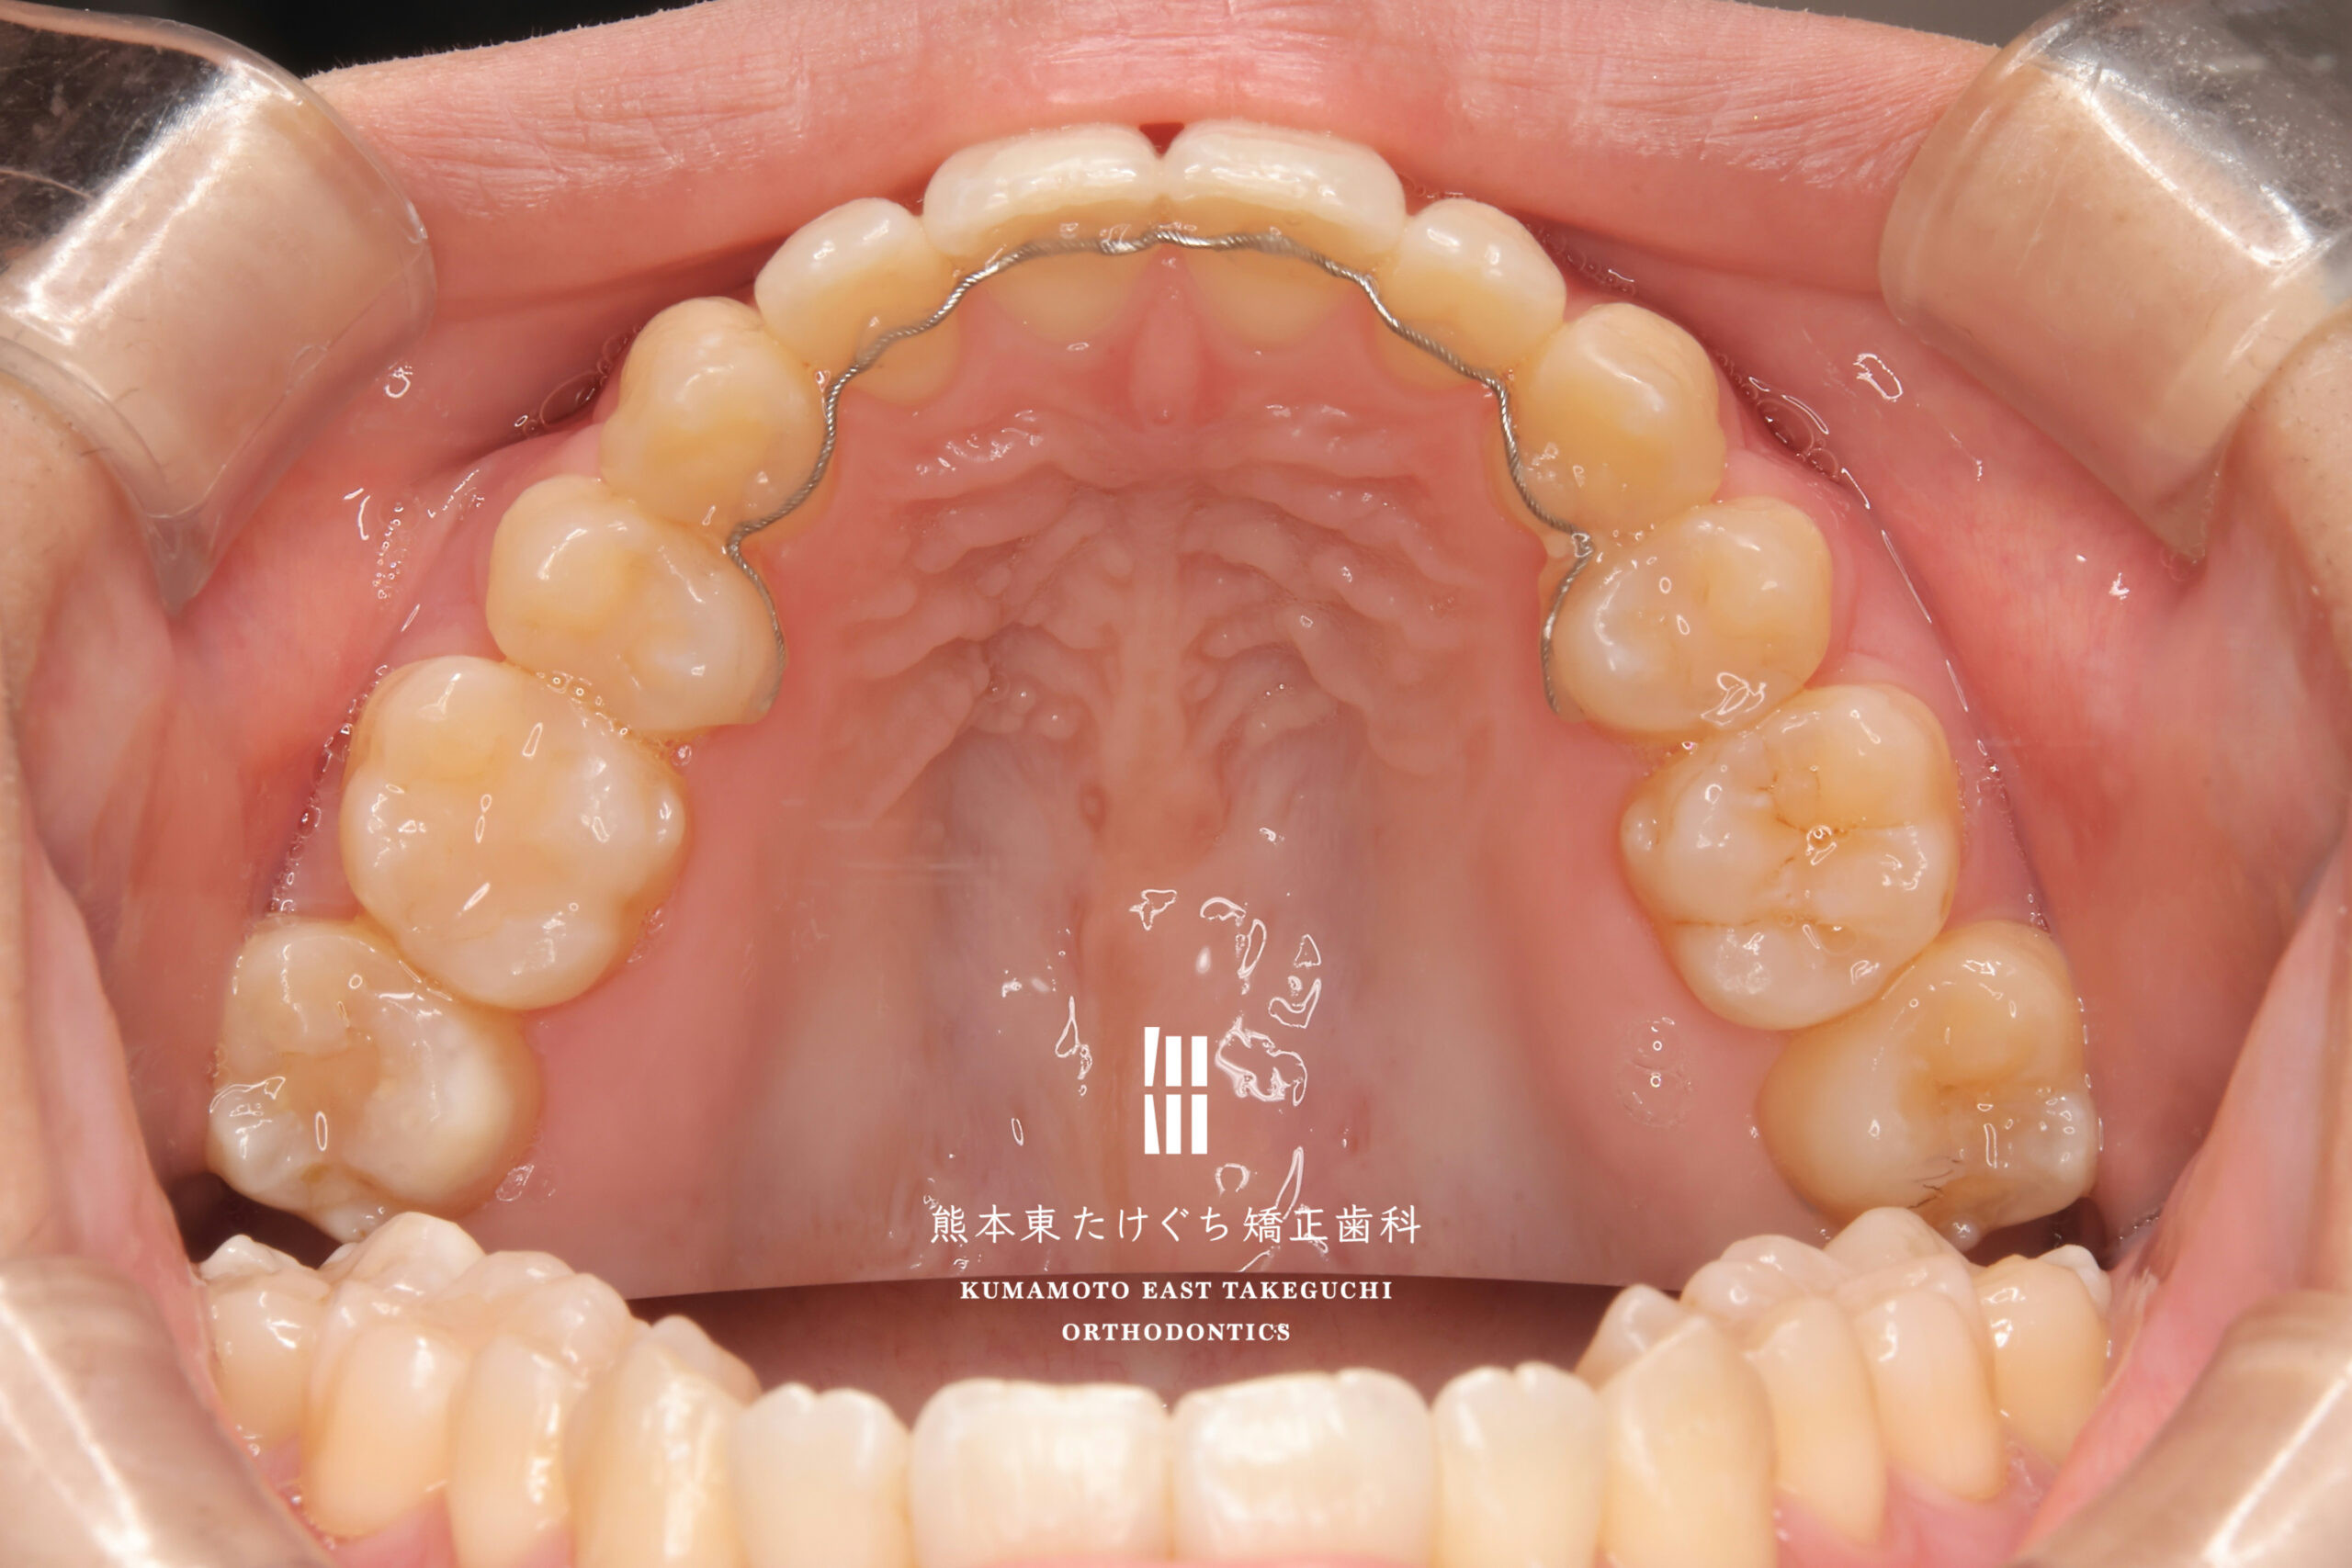

25歳女性 成人矯正 ガタガタ 開咬

主訴 八重歯、歯を閉じた時に隙間があく

治療内容 叢生を伴う開咬を改善するため、上の永久歯を2本と下の永久歯2本を抜歯し、固定式ワイヤー装置を用いて治療しました。

治療期間・回数の目安 2年1ヶ月

治療費 矯正基本料金693,000円(税込)+ 保定装置作製料金33,000円(税込)